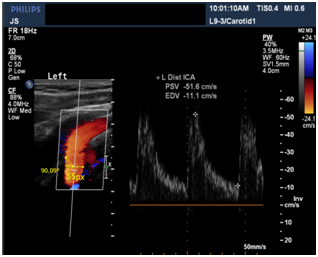

Input dicom images

In the demo version of Sante Dicom Viewer we can measure the radius only in pixels. To convert that to centimeters, calibration length of the image is considered and correspondingly a conversion factor is multiplied to get diameter in centimeters.

CL: Calibration length, which is 7cm in the image below.

Figure 4 Ultrasound image of Internal Carotid Artery.

365 is the measured length of the rectangle in pixels where the blood vessel is shown in ultrasound image (Figures 4-6).

Diameter(D)= 3.0*55 365*2 MathType@MTEF@5@5@+= feaagKart1ev2aaatCvAUfeBSjuyZL2yd9gzLbvyNv2CaerbuLwBLn hiov2DGi1BTfMBaeXatLxBI9gBaerbd9wDYLwzYbItLDharqqtubsr 4rNCHbGeaGqk0di9crFfpeea0xh9v8qiW7rqqrFfpeea0xe9Lq=Jc9 vqaqpepm0xbba9pwe9Q8fs0=yqaqpepae9pg0FirpepeKkFr0xfr=x fr=xb9adbaqaaeGaciGaaiaabeqaamaabaabaaGcbaqcLbsacaWGeb GaamyAaiaadggacaWGTbGaamyzaiaadshacaWGLbGaamOCaiaacIca caWGebGaaiykaiabg2da9OWaaSaaaeaajugibiaaiodacaGGUaGaaG imaKqzadGaaiOkaKqzGeGaaGynaiaaiwdaaOqaaKqzGeGaaG4maiaa iAdacaaI1aqcLbmacaGGQaqcLbsacaaIYaaaaaaa@4FF2@ cm=0.220602cm

After getting the input velocity (PSV) from the dicom images, we convert it to flow rate from the formula4 and as the current flows through the above circuit, flow rate at each segment is calculated and converted back to velocities to get the blood flow velocities. Similar to the above ultrasound image, 5 images at different points in CCA, ICA, and ECA respectively of the same patient were taken. And velocities at the points L2, L5 and L3 were calculated given velocities at L1 and L4 with ±5% errors based on the flow rate division with different Windkessel models stitched along the artery with the calculated radius from the images and assuming an average elasticity, thickness, viscosities and densities of the blood Figure 7.